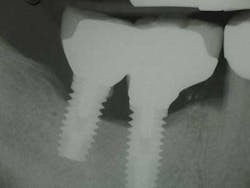

Fig. 1: Radiograph retained cement causing peri-implantitis.